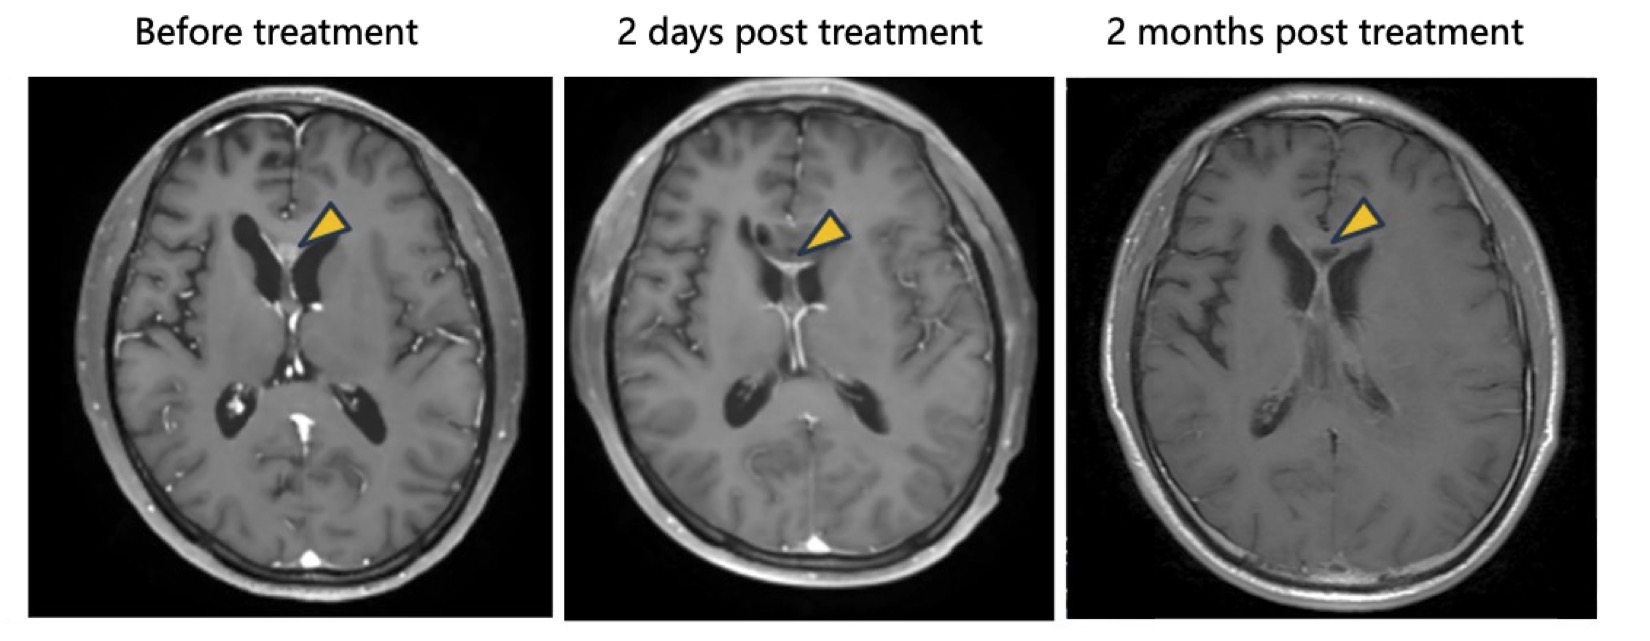

Tumor Response: The patient receiving intratumoral injection demonstrated a clear therapeutic effect, with significant regression of target lesion.